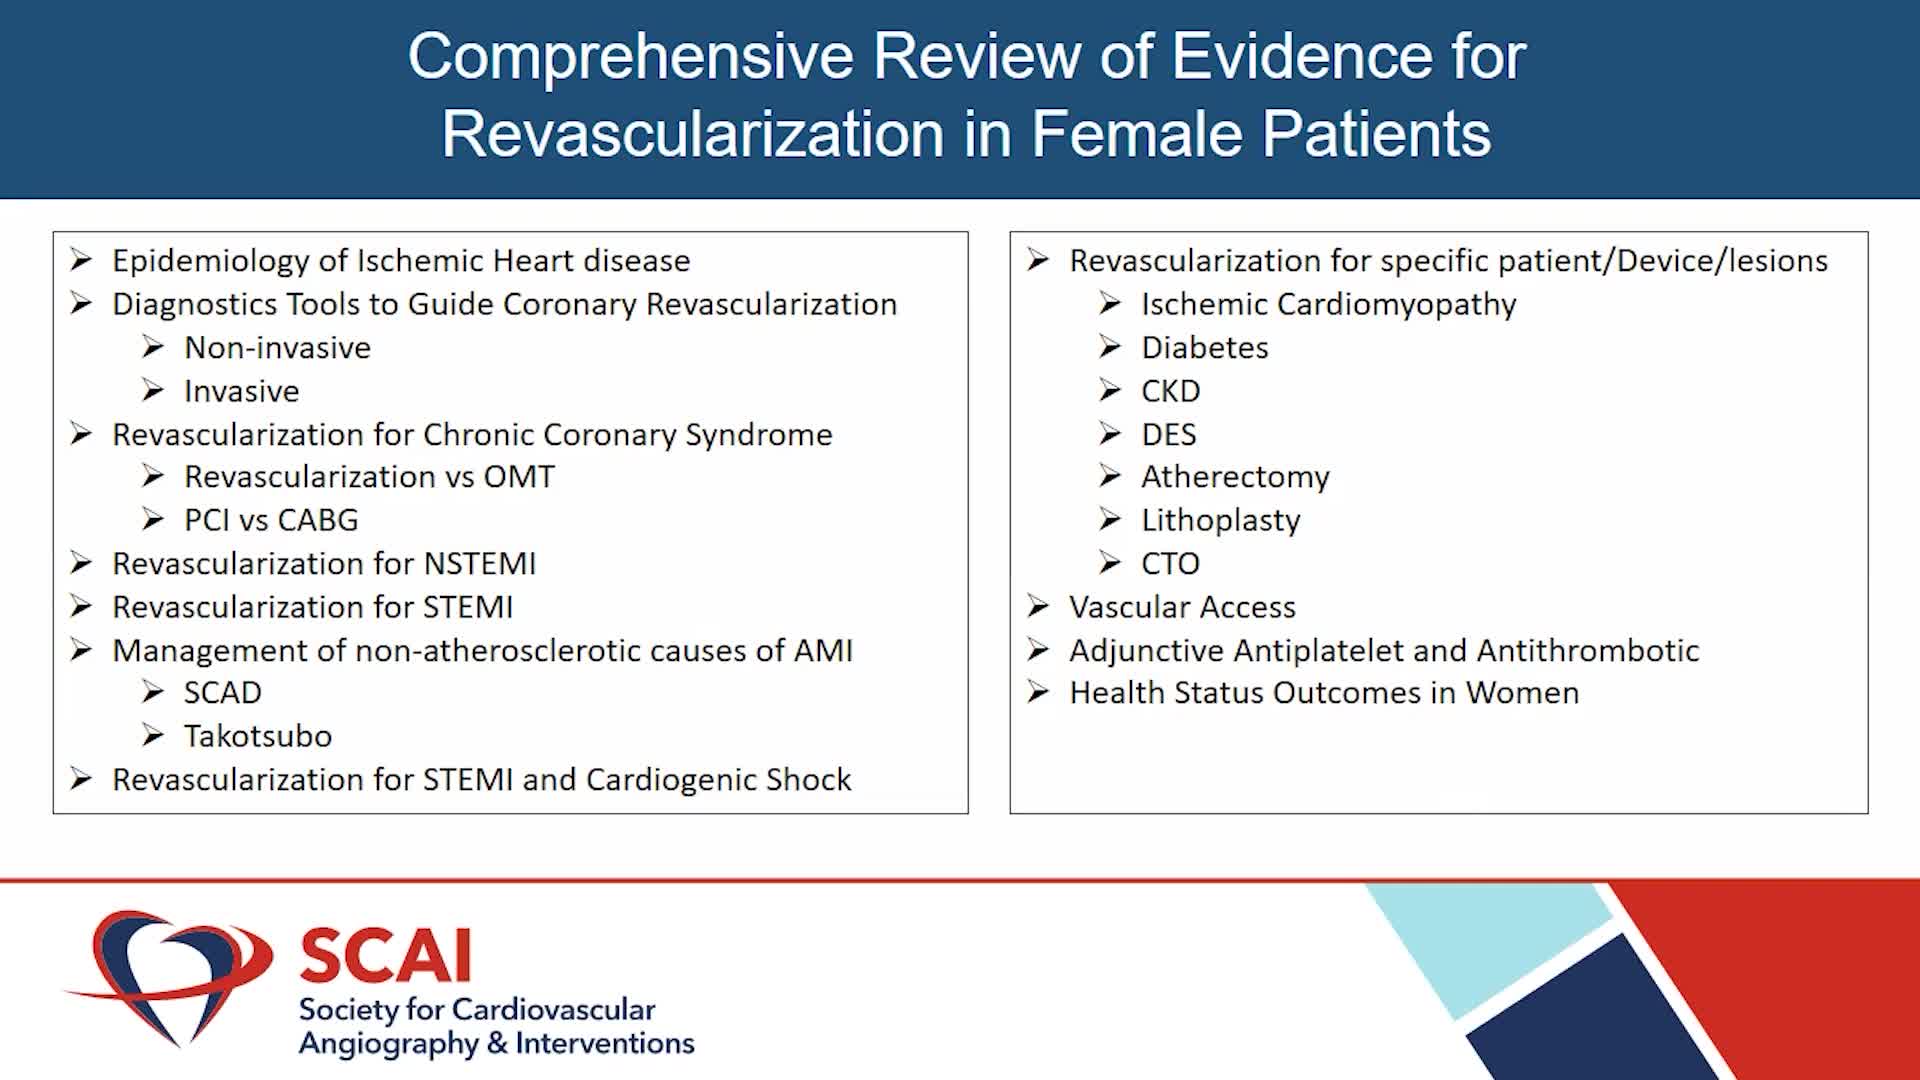

Simplify your procedures with Intravascular Lithotripsy (IVL) by safely modifying intimal and medial calcium to achieve optimal outcomes while minimising trauma, complications and costs due to its unique MOA.

Intravascular Lithotripsy for Treatment of Severely Calcified Coronary Artery Disease: The Disrupt CAD III Study

Shockwave IVL Coronary Real-World Cases, Outcomes & Algorithms: An InCathLab Webinar